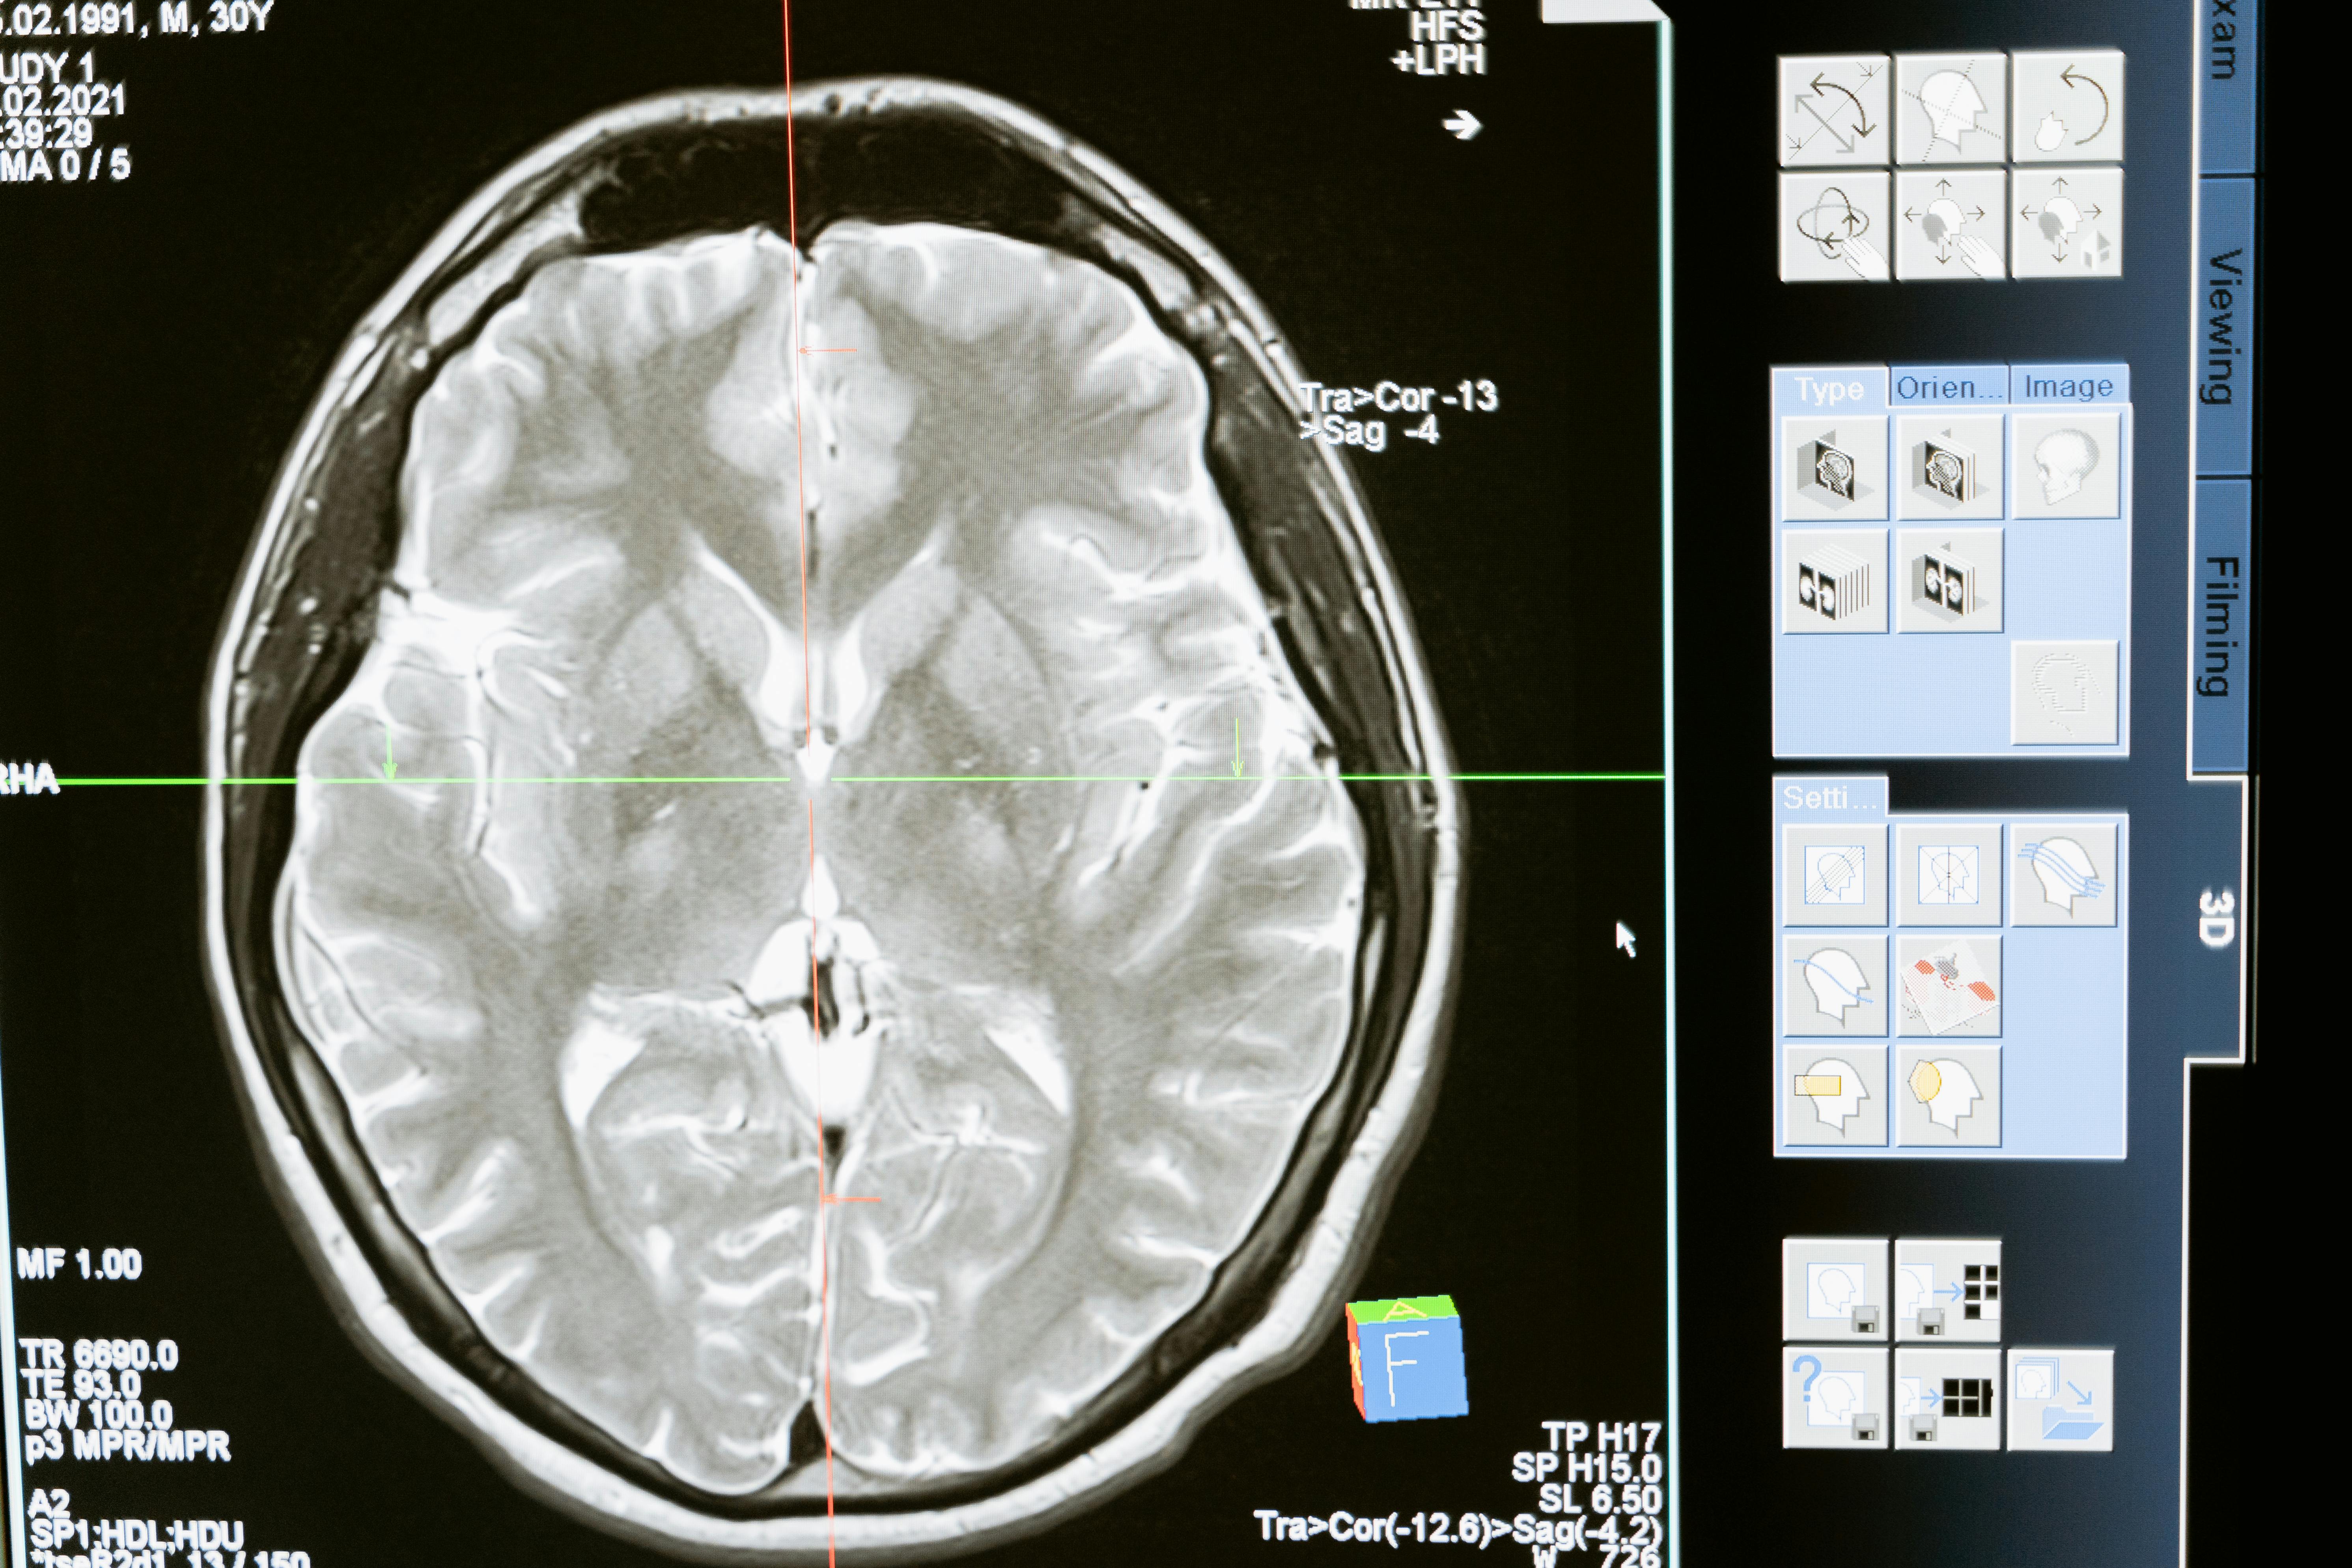

Le service de neurologie prend en charge les pathologies du système nerveux, grâce à une expertise approfondie et des équipements avancés. Nos examens permettent de diagnostiquer et suivre les affections neurologiques, en s’appuyant sur des explorations fonctionnelles de haute précision, garantissant des soins adaptés aux besoins spécifiques de chaque patient.